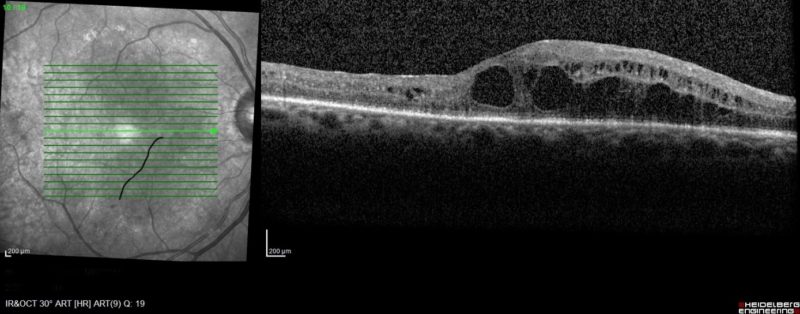

Seul un ophtalmologiste peut poser le diagnostic de rétinopathie ou de maculopathie diabétique. Un examen ophtalmologique complet est nécessaire avec réalisation d’un fond d’œil (après dilatation des pupilles).

Des examens complémentaires peuvent être indiqués en fonction des résultats de l’examen clinique :

- Tomographie à cohérence optique